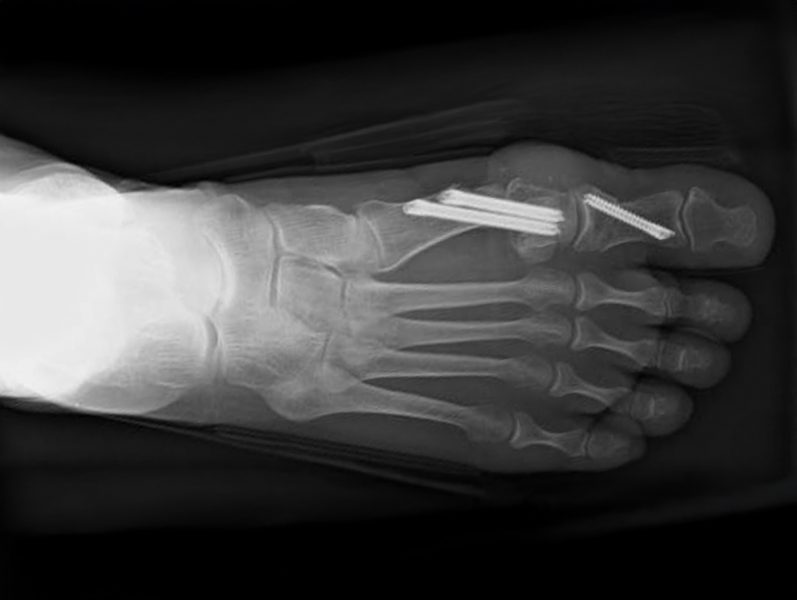

Fehlstellungen der Zehen sind ausgesprochen häufig, allen voran der Hallux valgus. Im frühen Stadium kann man üblicherweise mit gutem Schuhwerk, Einlagen und Fußgymnastik viel erreichen. Fortbestehende Beschwerden und fortschreitende Erkrankungen sind mit einer operativen Korrektur gut behandelbar. Hier nutzen wir zunehmend möglichst minimalinvasive Techniken (sogenannte „Schlüssellochtechnik“).

Korrektur von Fehlstellungen der Großzehe (Hallux valgus, Hallux varus)

Minimalinvasive OP-Techniken insbesondere bei Hallux valgus, Spreizfuß, Krallenzehen und Plattfuß